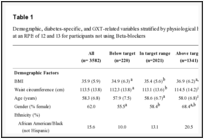

Diagnostic criteria are based mainly on clinical history, but genetic evaluation has been considered. According to the Danish Guideline for VHLD and Massachusetts General Hospital criteria, one should be diagnosed with VHLD if fulfill one or two conditions: 1- At least two of manifestations described below; 2- At least one of manifestations described below, and pathogenic mutation in VHL gene in genetic testing or at least one first-degree relative with VHLD. The manifestations that are considered in clinical diagnostic criteria are: hemangioblastoma of retina, cerebellum, medulla oblongata or spinal cord, endolymphatic sac tumor, clear renal cell carcinomas, pheochromocytoma, paraganglioma and/or glomus tumor, neuroendocrine neoplasms and/or multiple cysts of pancreas. If some of these manifestations are diagnosed in patients without family history of VHLD, the age of onset (< 30 years for hemangioblastoma and <40 years old for clear cell renal cell carcinomas or pheochromocytoma) or the number of lesions (usually bilateral or multiple in clear cell renal cell carcinomas or pheochromocitoma; more than two hemangioblastomas of central nervous system; more than one pancreatic serous cystadenoma or neuroendocrine tumor or multiple pancreatic cysts) should be considered as diagnostic criteria. In sporadic cases that do not satisfy any of these criteria, differential diagnosis should be remembered, such as polycystic kidney disease, multiple endocrine neoplasia (MEN) type 2, neurofibromatosis, hereditary pheochromocytoma-paraganglioma and others [5,13]. The disease can be divided into two types, depending on genotype-phenotype characteristics. Patients classified as type 1 have lower risk to develop pheochromocytomas than type 2. Type 2 is divided into three subgroups (A, B and C), which are defined by presence or not of clear cell renal cell carcinoma and/or hemangioblastoma [4]. Pancreatic neoplasms and cysts can be found in types 1, 2A and 2B, but the subgroup 2C is characterized by the exclusive presence of pheochromocytoma (Table 1) [4,13,20].

Table 1:

Clinical subtypes of VHLD based on genotype-phenotype characteristics.